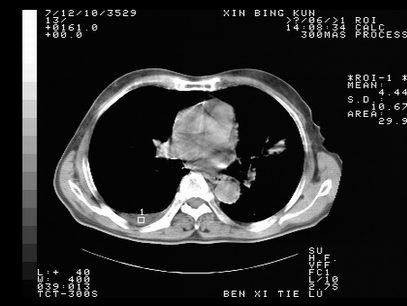

标题: CT10820:男,73岁,病史肺TB,现病史肺炎,直肠CA术后 [打印本页]

标题: CT10820:男,73岁,病史肺TB,现病史肺炎,直肠CA术后

双肺间质改变,依据病史双肺多发结节灶考虑转移,少量胸水.

1.两肺结核.2.两肺多发转移瘤.3右侧少量胸腔积液4.主动脉钙化.

双肺多发结节及条片状致密影,右侧少量胸腔积液。临床:直肠ca术后,肺tb病史。综合考虑:1 双肺转移!2 继发性肺结核合并感染!

此人病史较复杂,原有肺结核,直肠癌术后。肺部病灶形态亦呈多形性。因此,不可仅以一种病来解释肺部的病变。双肺多发的类圆形结节灶,结合病史还是首先考虑转移瘤,而双肺其余病灶还需结合化验室检查,结核或肺部感染在无其它检查资料的情况下不好排除。还是那句话----放射科医生不是开照像馆的,我们也是医生,看片一定要多结合临床及其它检查资料。要当一名合格的放射科医生,并不比当一名临床医生容易,我们可别把自已不当医生看。

两肺多发结节影,并见滋养动脉与其相连,考虑 两肺转移. 右侧胸腔积液考虑胸膜转移.

左肺上叶下叶背段,右肺中下叶见多发斑片状、条索状高密度影,兵变周围小结节影形成“树芽”样改变。 左肺上叶舌段近前胸壁处及右肺中叶内侧段见结节影。右侧胸膜腔内见液体密度区。纵隔内未见明确增大淋巴结。考虑左肺上叶舌段近前胸壁处及右肺中叶转移瘤可能性大。两肺继发型肺结核。右侧胸腔积液。